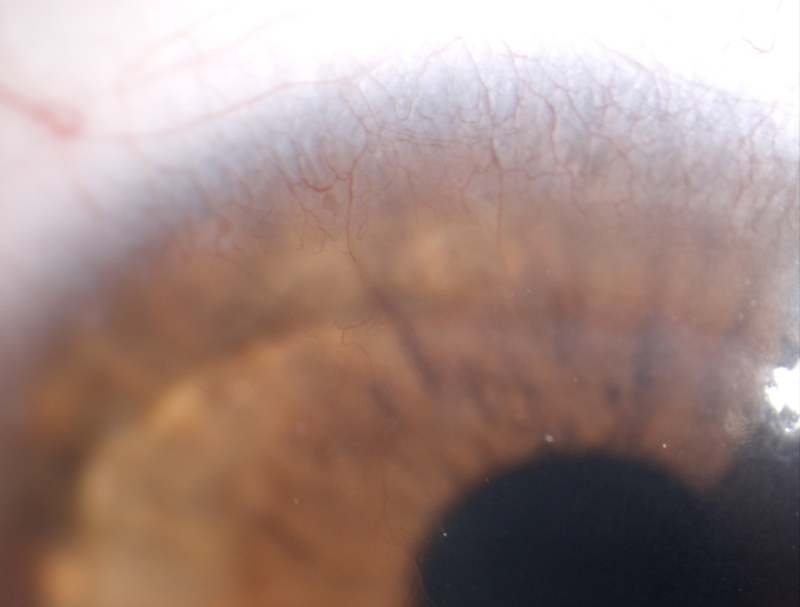

Gent.mo dottore, le invio nuova foto del suo paziente in riferimento al vaso corneale fatta proprio oggi.

Gentile Signore, la lente secondo me va bene... ha un buon appoggio, una buona dinamica e un discreto centraggio (difficile ottenere di meglio se è presente una lieve asimmetria della cornea). L'importante a mio parere è tenere sotto stretto controllo la condizione affinché non aumenti o non entri nel lembo la neovascolarizzazione sia per ragioni ipossiche che per stimoli meccanici. Cordiali saluti.